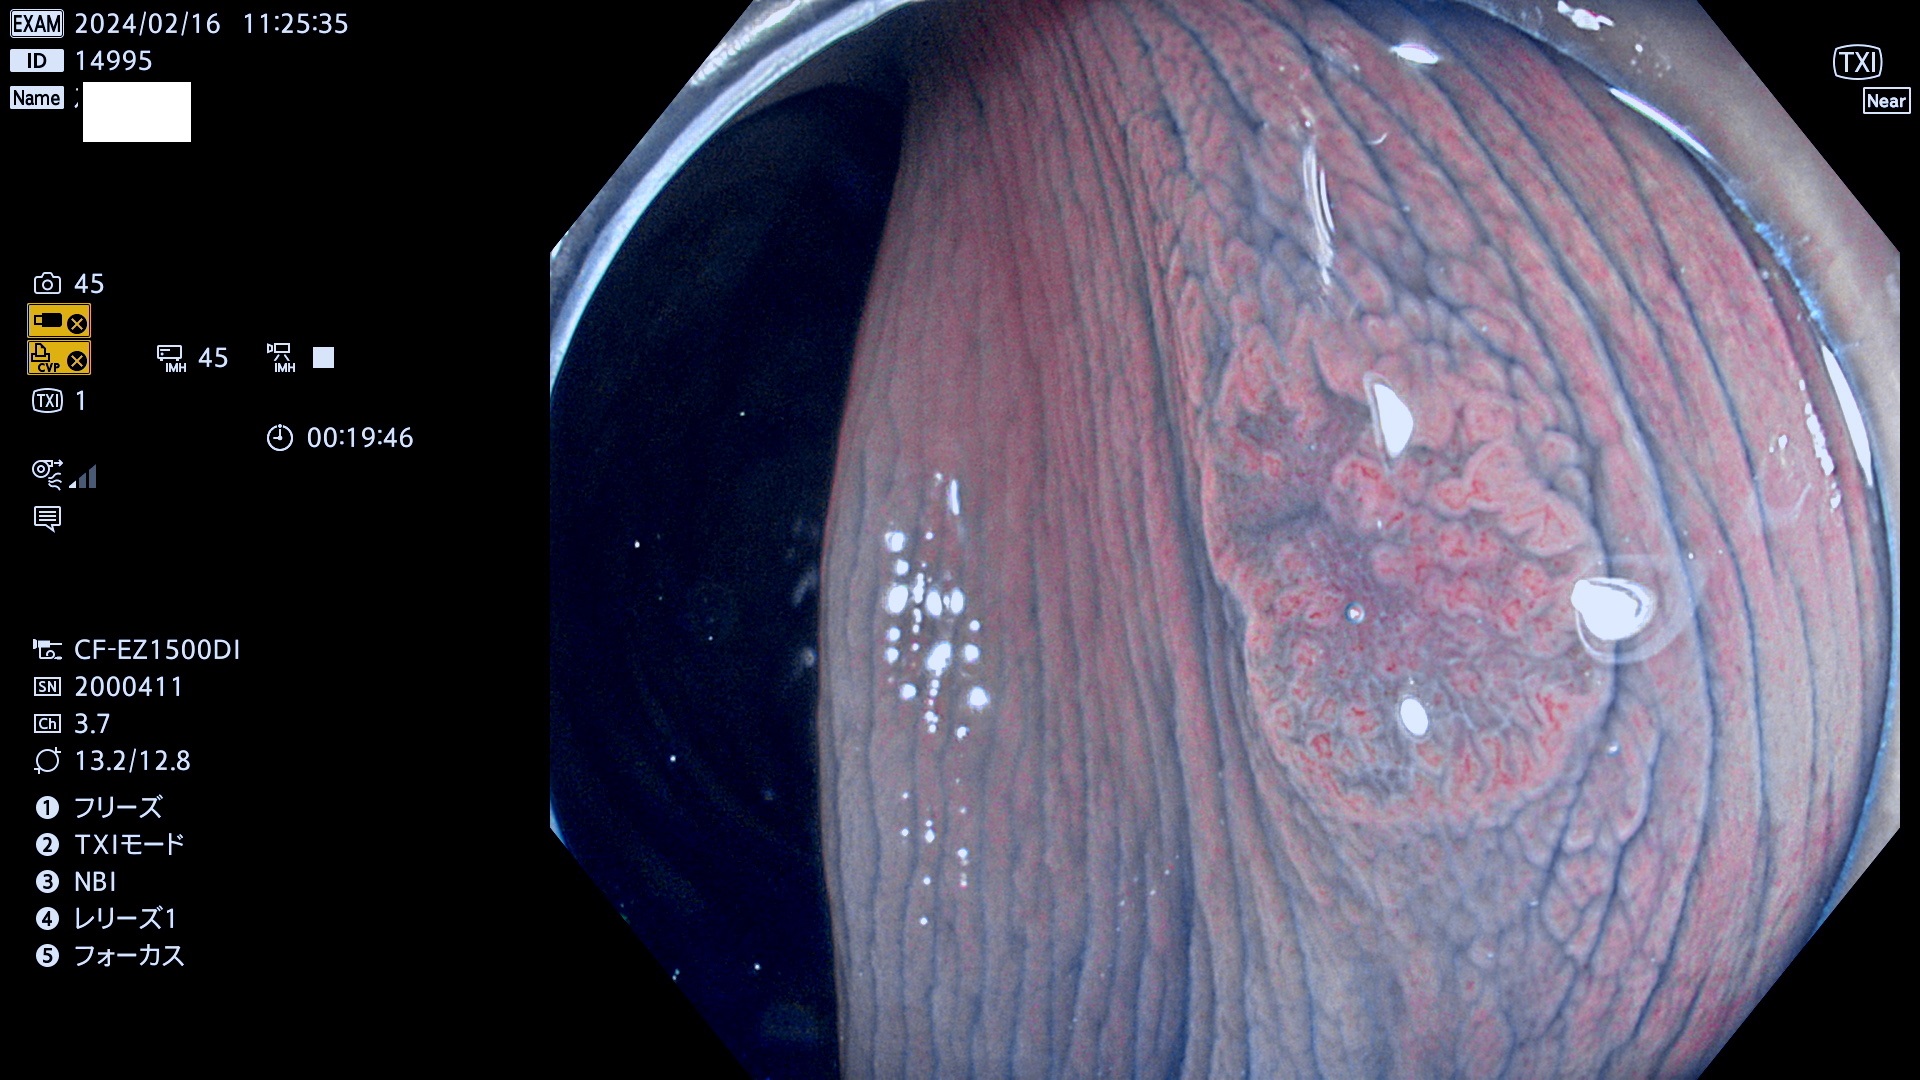

表面型腺腫(Flat Adenoma)の中で、完全に平坦な物をUb、陥凹している物をUcと呼びます。平坦隆起型(Ua)よりも、発見が難しく危険な病変です。

毎週の検査(木・金・土・日)に発見されたUb、Uc型・腺腫を、その週の日曜の夜にUPし1週間、提示します。

抽出の対象期間 2024年2月15日(木)〜2月18(日)の4日間(40件の検査)10件 (10/40=25%)